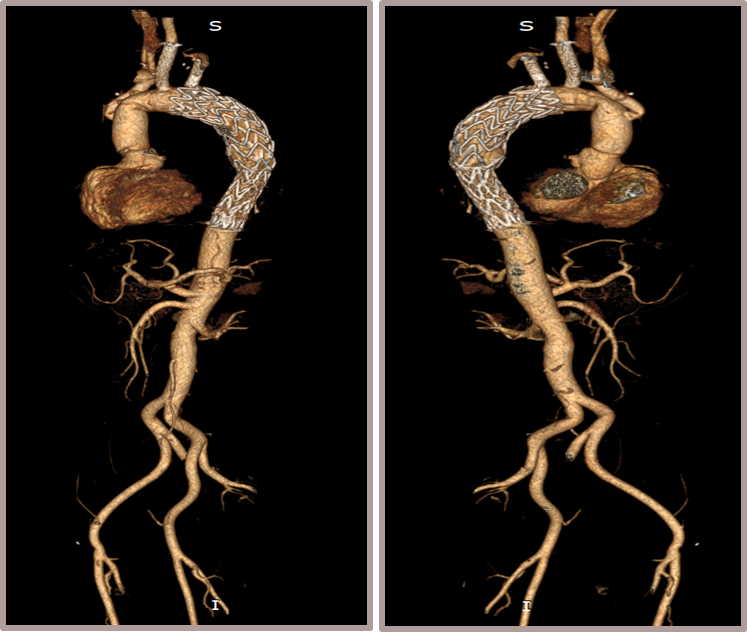

夹层动脉瘤CTA:A型主动脉夹层,初破口位于主动脉弓近端,逆撕至主动脉根部,左颈总动脉及左锁骨下动脉根部受累,夹层远端累及至双侧髂动脉。

术前影像

置入双分支术中支架

术后影像